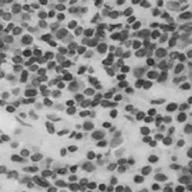

胡青牛心中不由得赞叹:果然是一条好汉。于是在CT的引导下进行了T6病变的活检。出乎意料的是,活检结果证实诊断为低度恶性非霍奇金淋巴瘤(NHL)。另外,免疫组织化学染色显示B细胞标记物CD20,CD45和CD79a呈阳性,支持低度淋巴瘤的诊断。

图2 取自T6病变的活检组织(HE染色,×20倍)。单一混合大小淋巴细胞群浸润,与非霍奇金淋巴瘤一致。